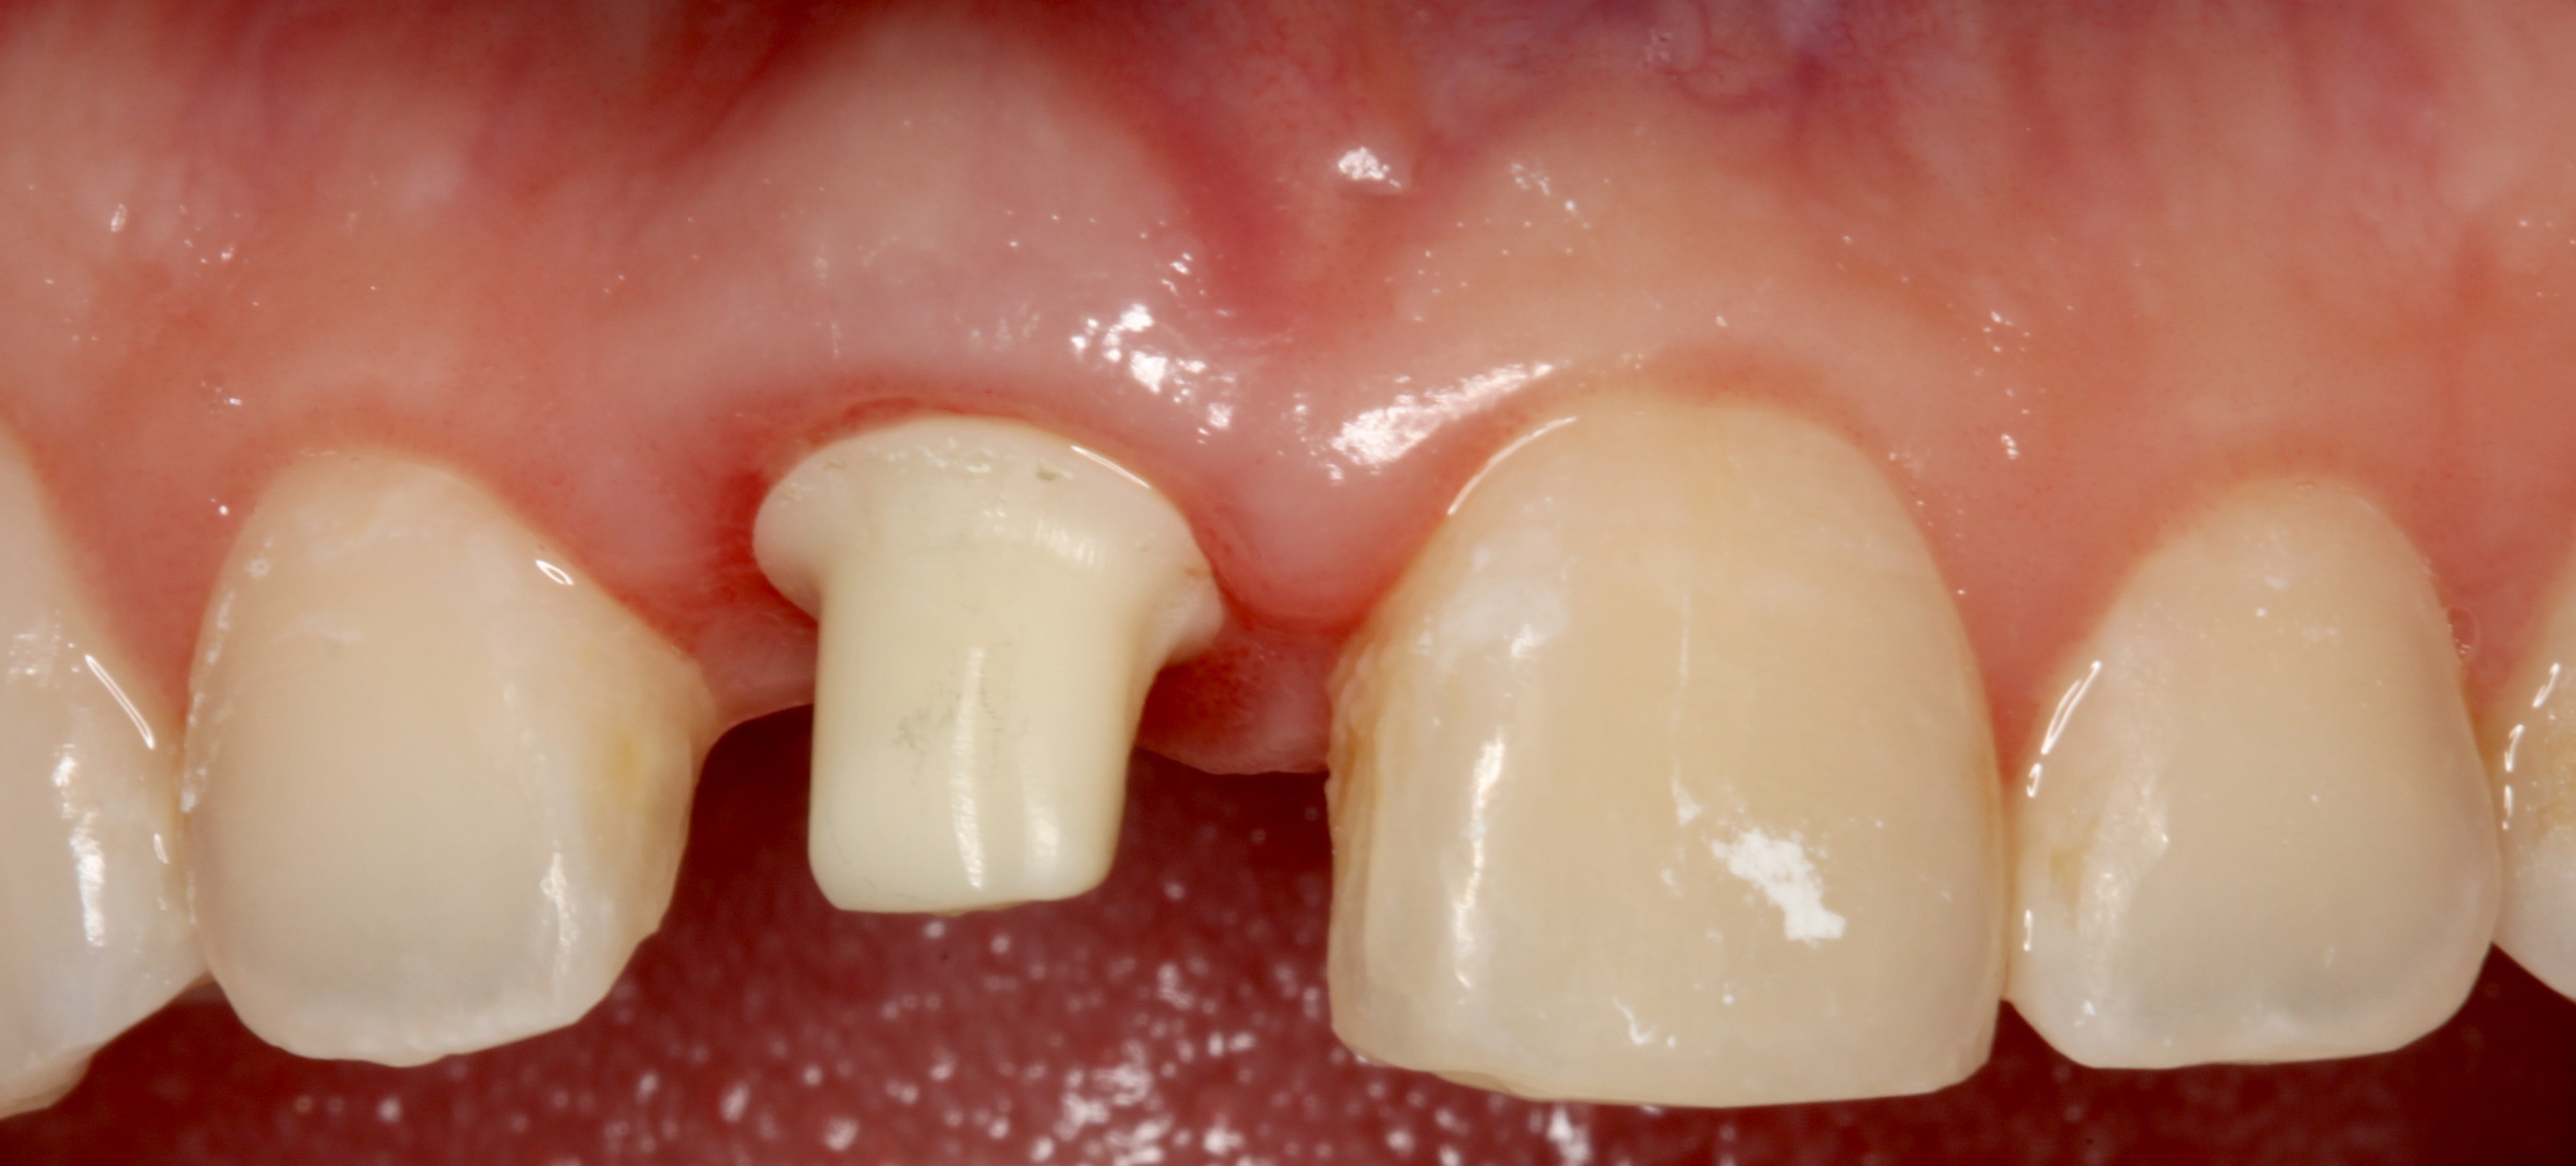

Plugging into digital workflows provides opportunities to integrate CAD/CAM technologies at every step of the treatment process for dental implants. In another example, a patient presented with a failing tooth No. 8 (Figure 6 and Figure 7). After discussing treatment options, the patient chose to forgo any treatment to address tooth and soft-tissue asymmetries and wanted to proceed with a dental implant-supported restoration without additional treatment. After integrated 3-dimensional planning, the tooth was extracted, and then an implant and the final custom CAD/CAM abutment (titanium base with zirconia supra-structure) were placed with a provisional restoration in the same visit (Figure 8 and Figure 9). Soft-tissue grafting was also done at the same visit to address the deficient buccal tissue height on No. 8 (Figure 10). At 3 months, the patient presented for the final restoration, with excellent healing around the implant (Figure 11) and soft-tissue healing guided by the custom abutment (Figure 12).

Fig 9. Final custom abutment for tooth No. 8 in place with a provisional resin restoration that had been milled before surgery.

Figure 9